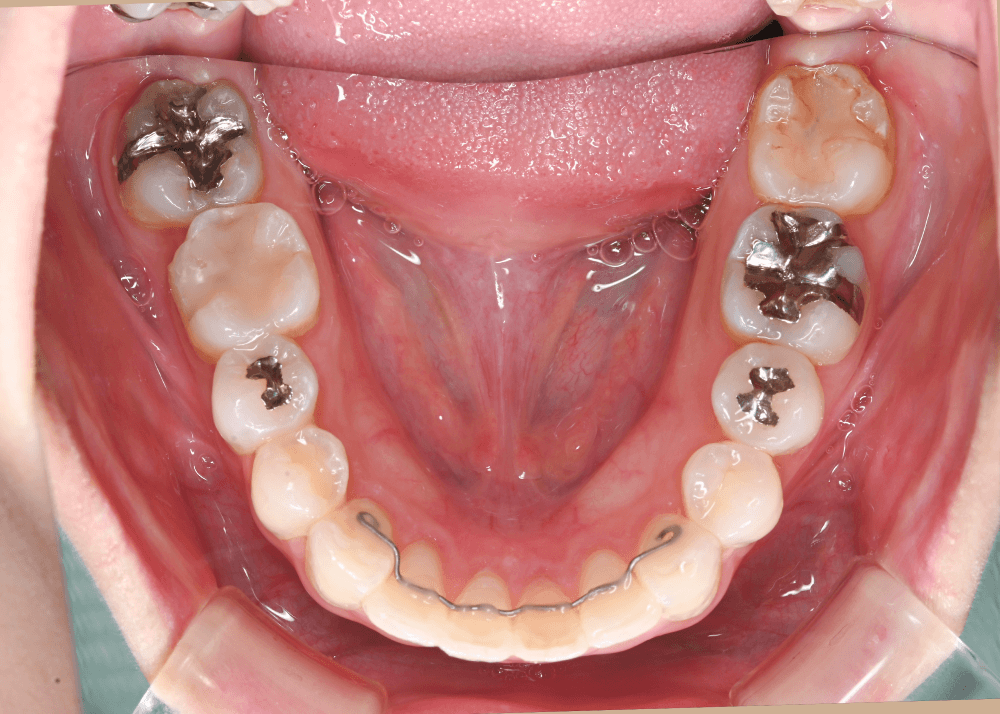

リンガルアーチの併用

歯列全体を前方へ移動させる際には、

アーチ形態を維持するための補助装置としてリンガルアーチを併用しました。

これにより歯列の形を安定させながら、

上下の噛み合わせを維持したまま歯列を前方へ移動させることが可能になります。

治療後の変化

治療後は、舌側に倒れていた前歯の傾きが改善しています。

・上下前歯のなす角(Interincisal angle)

138° → 125°

前歯のポジションが適正化されたことで、スマイル時に奥まって見えていた歯の見え方が改善し、より自然な印象になっています。

また、唇を内側から支える「口唇サポート」が回復し、横顔の印象にも変化がみられました。